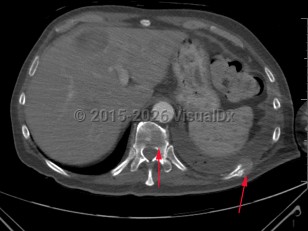

Psoas abscess

Spinal epidural abscess

Tuberculous spondylitis